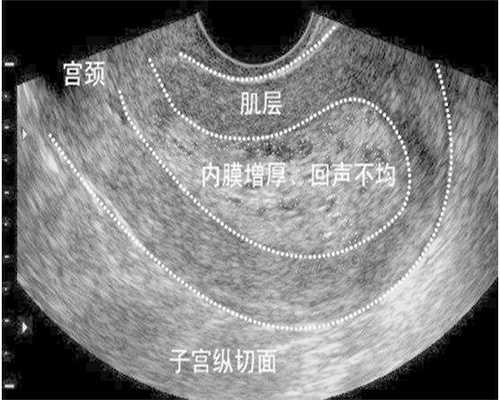

此外,女性还可以购买排卵试纸,来监测排卵情况,这是比较方便的,不过女性要正确的使用,以免让结果出现偏差。当然了,女性也可以去医院进行b超来明确。有些女性排卵时会觉得腰酸,而且也会出现下腹轻微疼痛的症状,此外还可能会有少量阴道出血现象,这些都是比较常见的,等排卵期过后就会慢慢消失。